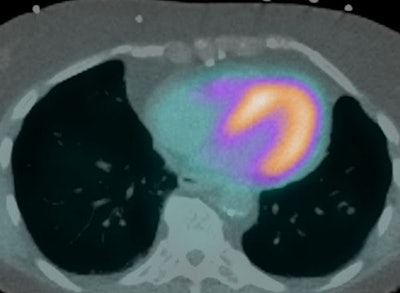

The American Society of Nuclear Cardiology (ASNC) and three partner societies have offered new guidelines for the use of CT in hybrid nuclear/CT cardiac imaging, as published September 2 in the Journal of Nuclear Cardiology.

The guidelines are intended to answer cardiac imagers' questions and guide them on SPECT/CT and PET/CT imaging with attenuation correction, localization of radiotracer uptake, and coronary artery calcium scoring, the ASNC said. The ASNC collaborated with the American Association of Physicists in Medicine, the Society of Cardiovascular Computed Tomography, and the Society of Nuclear Medicine and Molecular Imaging on developing the guide.